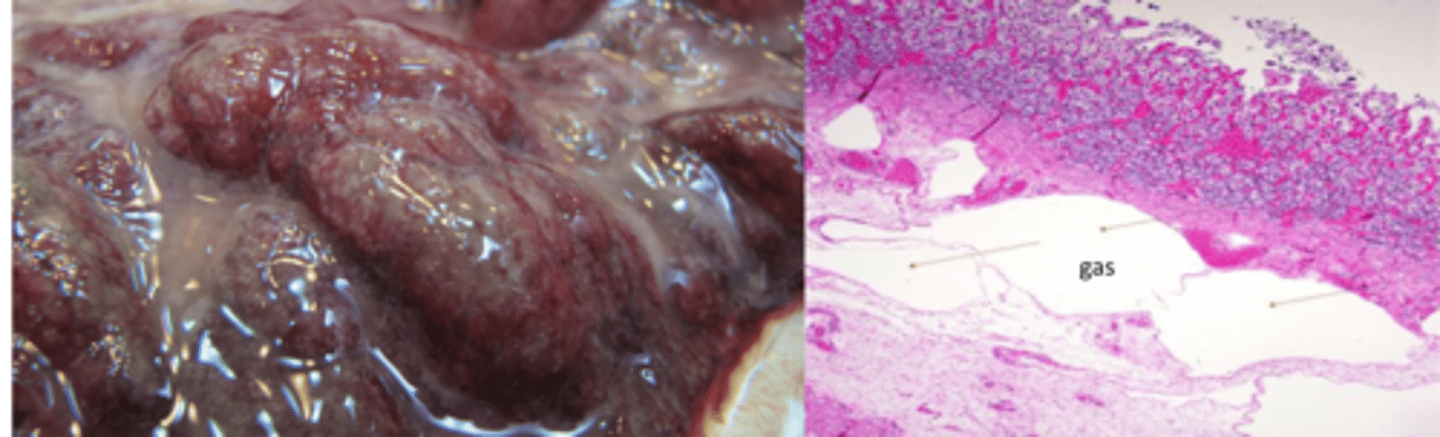

What agent will kill calves that are 2-6w old after short sings of abdomen distention?

Clostridium septicum/ perforinges

What lesions will you see in the abomasum of calves affected by C. perferingens or septicum?

Hemorrhage

Necrosis

Gas bubbles